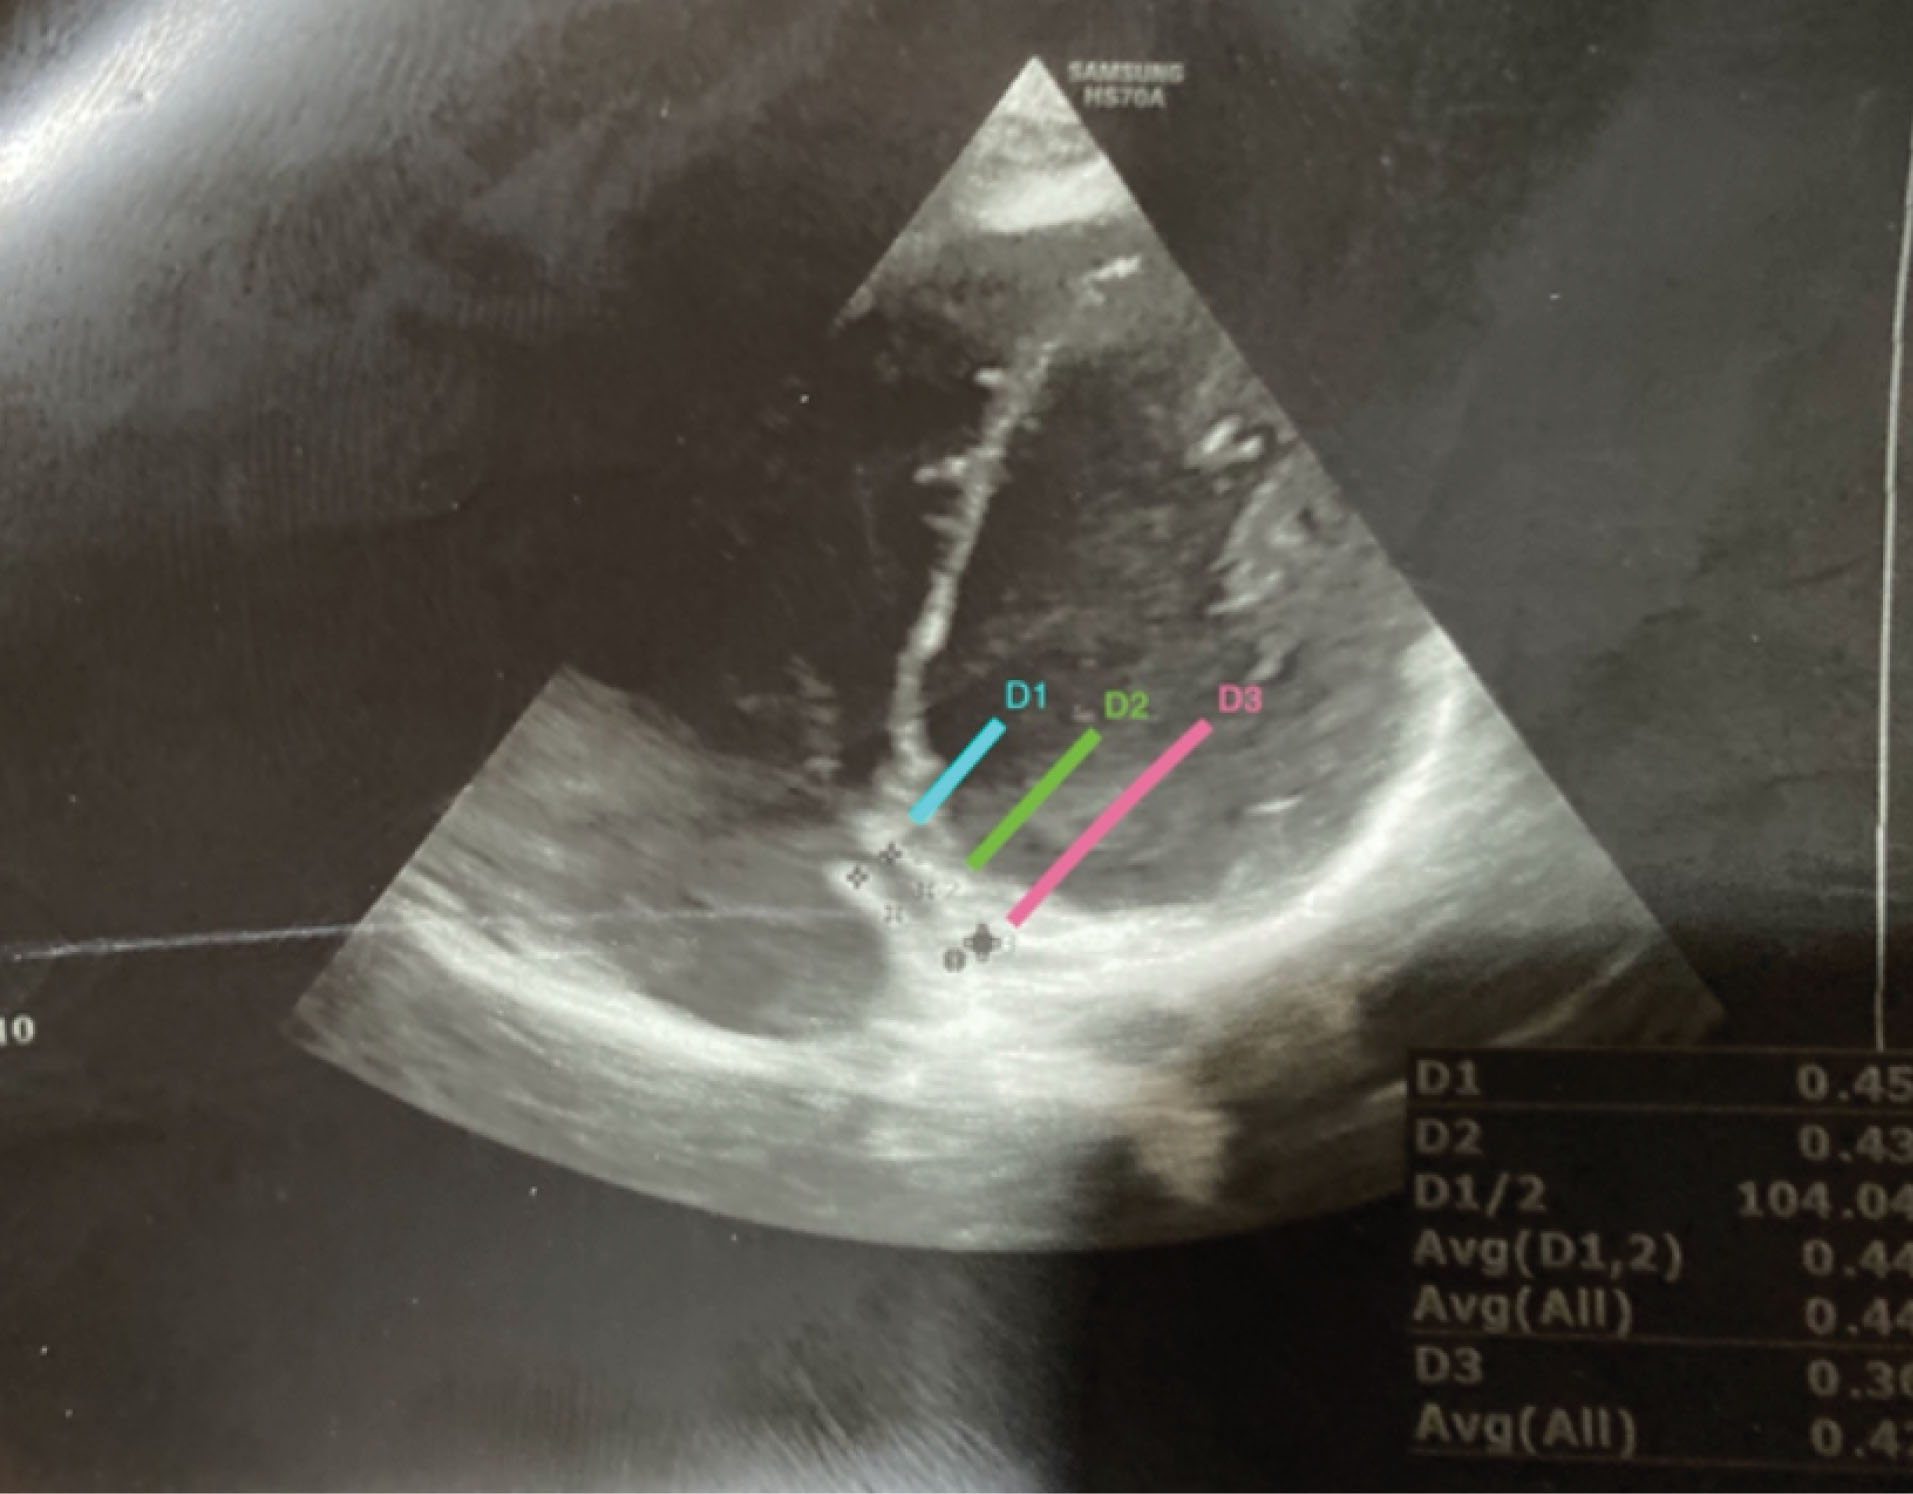

The superior and inferior diameters of CS were measured in the maximum dimension in three places (D1, D2, D3), while D1 was the diameter of CS 5 mm from the junction of the right atrium, D2 was the diameter of the middle part of CS and D3 was the diameter of the end part of CS (Figure 1).

aim-24-804-g001

Figure 1.

Coronary Sinus in 4-Chamber view.